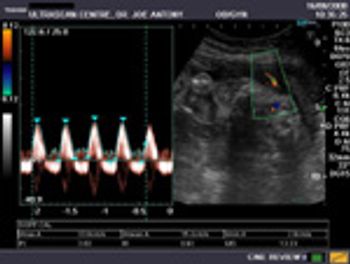

These ultrasound images show right hydroureter with hydronephrosis. What else do you see and what is the cause?